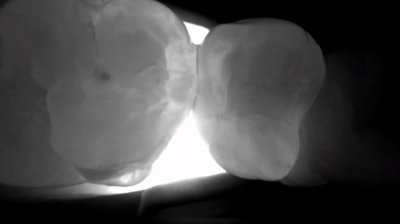

Interproximal decay, 25 years ago, when I was a dental student, was pretty cut and dry. The lesion, noted in a bitewing radiograph, was an indication of a cavity, and it needed to be drilled out and filled with a class II restoration. This meant that, if I showed the radiograph below to my clinical preceptor and suggested that we would have to do three fillings, my instructor would nod, give me the green light, and I would then commence the following:

Figure 4: Traditional bitewing radiography indicates clear decay on tooth #13, with some evidence of incipient lesions on #s 12, 14, 18, 19, 20, and 21. It is quite possible for me to miss one or more of these lesions on the lower teeth during busy times at the office.Figure 4: Traditional bitewing radiography indicates clear decay on tooth #13, with some evidence of incipient lesions on #s 12, 14, 18, 19, 20, and 21. It is quite possible for me to miss one or more of these lesions on the lower teeth during busy times at the office.

Using the same radiograph from above (Figure 8), I transilluminated the questionable areas, yielding highly accurate discernment of the extent and location of various cavities.